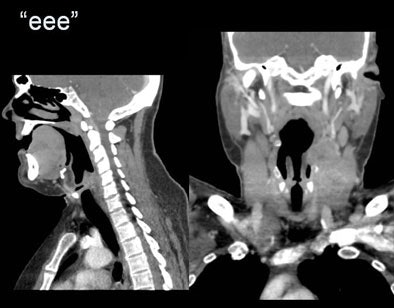

| Reconstructed images acquired with the "eee" technique demonstrate pyriform sinuses and apposed vocal cords in a squamous cell carcinoma patient imaged postchemotherapy. |